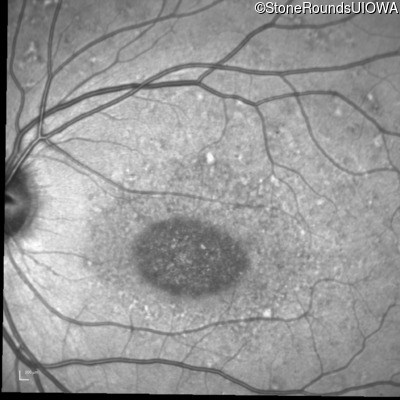

Infrared Fundus Photograph - Left - 20/125 sc

Exemplar